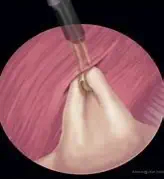

Gastropexie nur per Laparoskopie:

Dabei wird die Magenwand mit Hilfe einer Kamera und weiterer Instrumente vollständig von innen an die Bauchdecke genäht.

Diese Methode erfordert die notwendige Erfahrung des Chirurgen und wird sicher nicht in jeder Tierklinik durchgeführt.